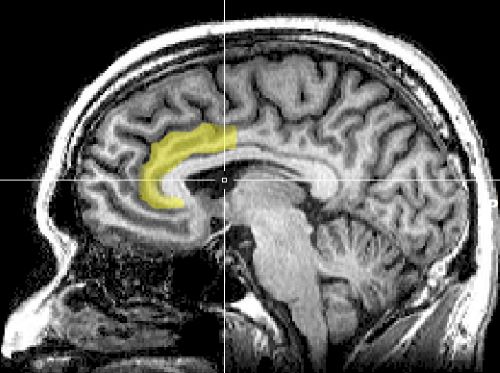

- Mindfulness meditators showed greater activation of rostral anterior cingulate cortex (ACC) and dorsal medial prefrontal cortex (MPFC).[6] This suggests that meditators have a stronger processing of conflict/distraction and are more engaged in emotional regulation. However, as the meditators become more efficient at focused attention, regulation becomes unnecessary and consequentially decreases activation of ACC in the long term.[7]

- The cortical thickness in the dorsal ACC was also found to be greater in the gray matter of experienced meditators.[8]

The ACC detects conflicting information coming from distractions. When a person is presented with a conflicting stimulus, the brain initially processes the stimulus incorrectly. This is known as error-related negativity (ERN). Before the ERN reaches a threshold, the correct conflict is detected by the frontocentral N2. After the correction, the rostral ACC is activated and allows for executive attention to the correct stimulus.[11] Therefore, mindfulness meditation could potentially be a method for treating attention related disorders such as ADHD and bipolar disorder.

- Mindfulness meditation regulates emotions via increased activation of the dorso-medial PFC and rostral ACC.[6]

Lateral prefrontal cortex (lPFC) is important for selective attention while ventral prefrontal cortex (vPFC) is involved in inhibiting a response. As noted before, the anterior cingulate cortex (ACC) has been noted for maintaining attention to a stimulus. The amygdala is responsible for generating emotions. Mindfulness meditation is believed to be able to regulate negative thoughts and decrease emotional reactivity through these regions of the brain. Emotion regulation deficits have been noted in disorders such as borderline personality disorder[22] and depression.[23] These deficits have been associated with reduced prefrontal activation and increased amygdala activity, which mindfulness meditation might be able to attenuate.